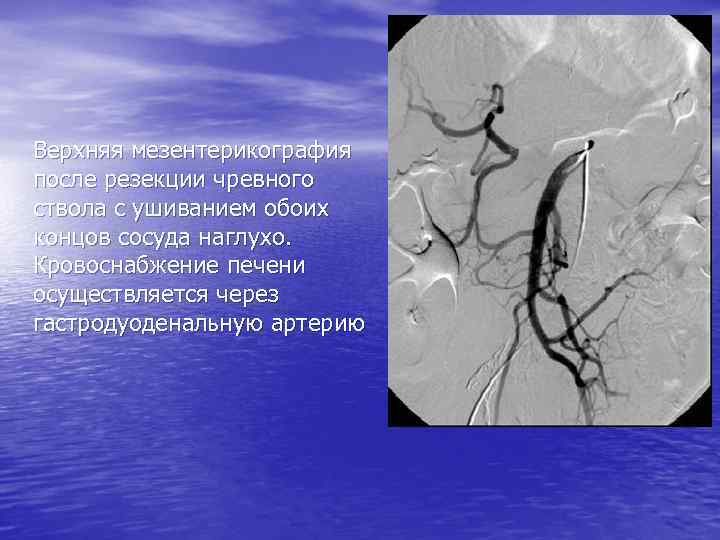

Верхняя мезентерикография после резекции чревного ствола с ушиванием обоих концов сосуда наглухо. Кровоснабжение печени осуществляется через гастродуоденальную артерию